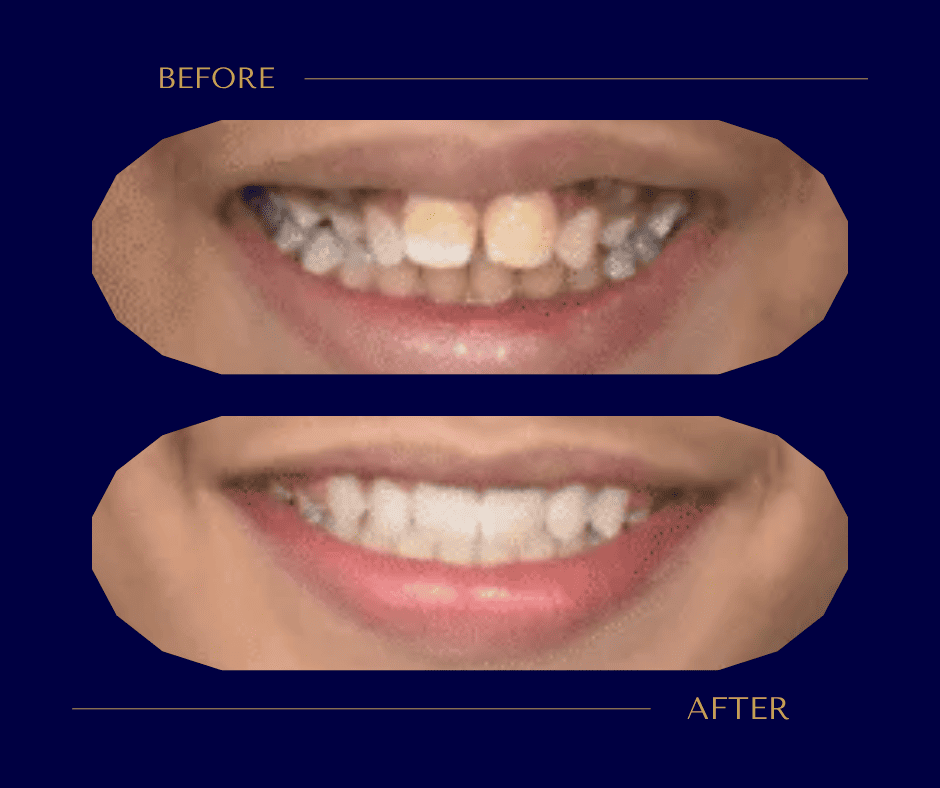

من الناحية الصحية، يُحسّن التقويم الإطباق، ويُخفف الضغط على مفصل الفك (TMJ)، ويُسهّل تنظيف الأسنان مما يقلل خطر التسوس وأمراض اللثة، وفي حالات بعينها يُحسّن النطق والتنفس. أما من الناحية الجمالية والنفسية، فلا شك أن انتظام الأسنان يُحدث أثراً بالغاً في الثقة بالنفس. يمكنكم الاطلاع على حالات قبل وبعد التقويم لترون الفارق بأنفسكم.